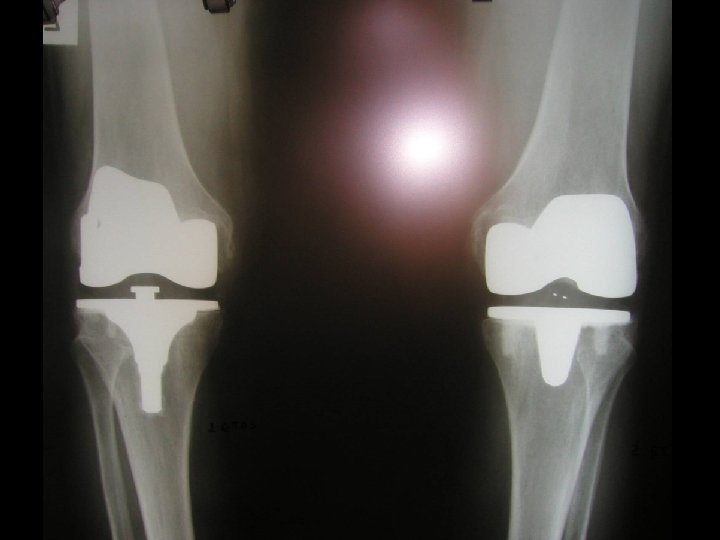

Our experience 527 total knee replacements with mobile bearing Period 1987 - 2005 48% left knee, 52% right knee 94 male, 433 female

ΤΥΠΟΣ ΑΡΘΟΠΛΑΣΤΙΚΗΣ n CEM/ED CEM/LESS CEM/ED TIBIAL TACK 80 0 0 80 LCS 276 30 162 84 GENESIS II M. b 171 27 0 144